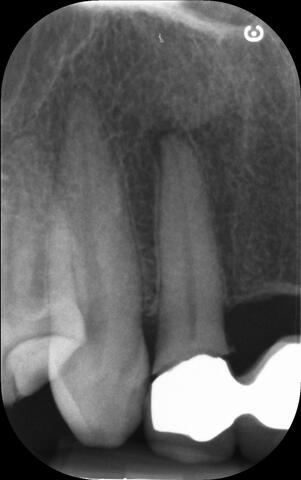

I am pleased to take endodontic referrals. Curved canals >30 degrees and potentially greater than 50 degrees can be negotiated. Sclerosed canals accessed. Post spaces prepared and the patient returned to you ready to restore.In most cases existing crowns, bridges and veneers can be retained with the endodontic access aesthetically restored after the full canal network has been treated.In the first instance I would prefer a radiograph and a brief list of patient expectations and a tooth history.

I really enjoy undertaking root canal treatments - rising to the challenge and helping people out of dental pain for the long term.I was privileged to be asked to speak at the 2016 BDA Conference, where I have a lecture about providing quality endodontic outcomes to patients, working as a generalist. Avoiding problems and pitfalls and maximising efficiency. One of the main matters that he covered was understanding that what is seen on plane radiography is utterly misleading and should not be the criteria by which a generalist continues treatment once it has been started.

At the 2016 BDA Conference, Thomas spoke about providing quality endodontic outcomes to patients, working as a generalist. Avoiding problems and pitfalls and maximising efficiency. One of the main matters that he covered was understanding that what is seen on plane radiography is utterly misleading and should not be the criteria by which a generalist continues treatment once it has been

started.